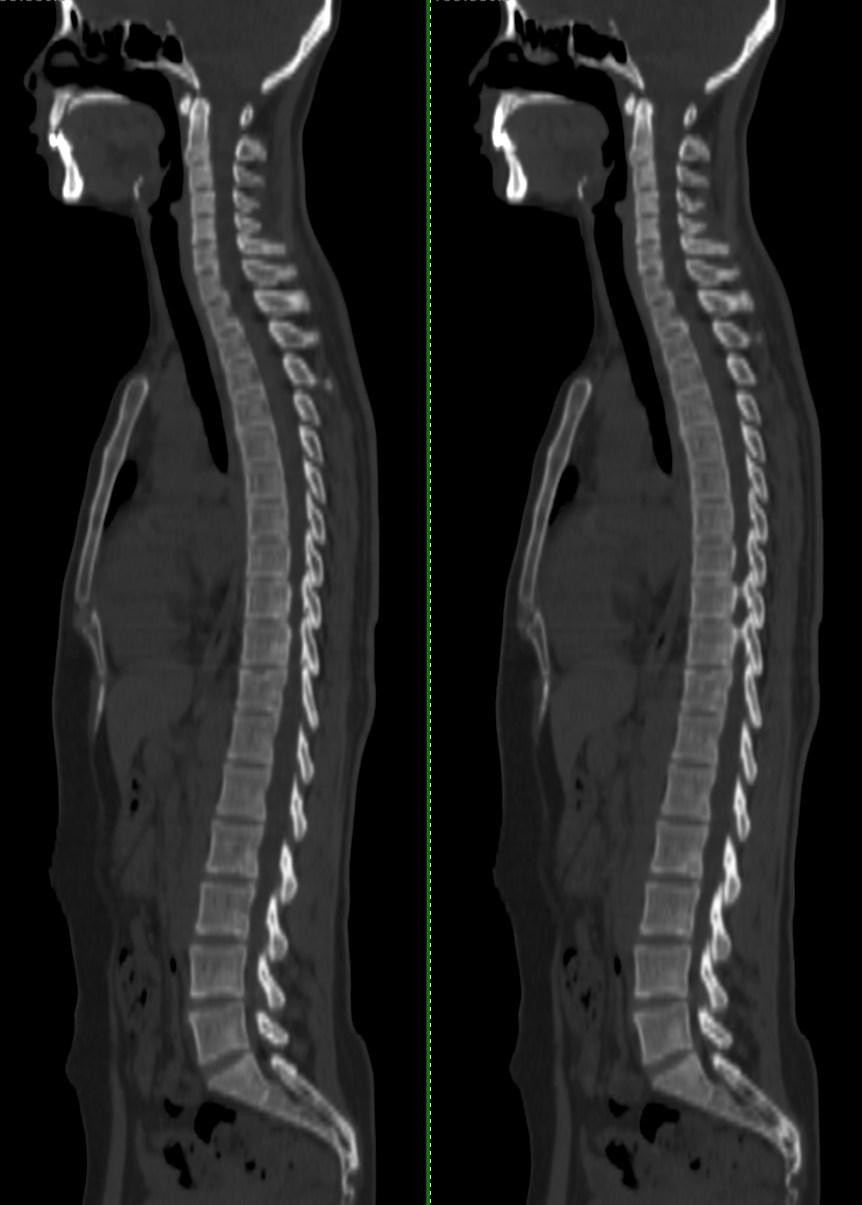

图1:正常成人(40岁)脊柱:↓

脊柱形态完整,生理曲度正常。椎体形态分布正常,椎间隙无狭窄,椎间盘内密度均匀,未见气体及其他异常密度影。椎体与椎间隙清晰,椎体边缘未见骨质硬化及增生。↓